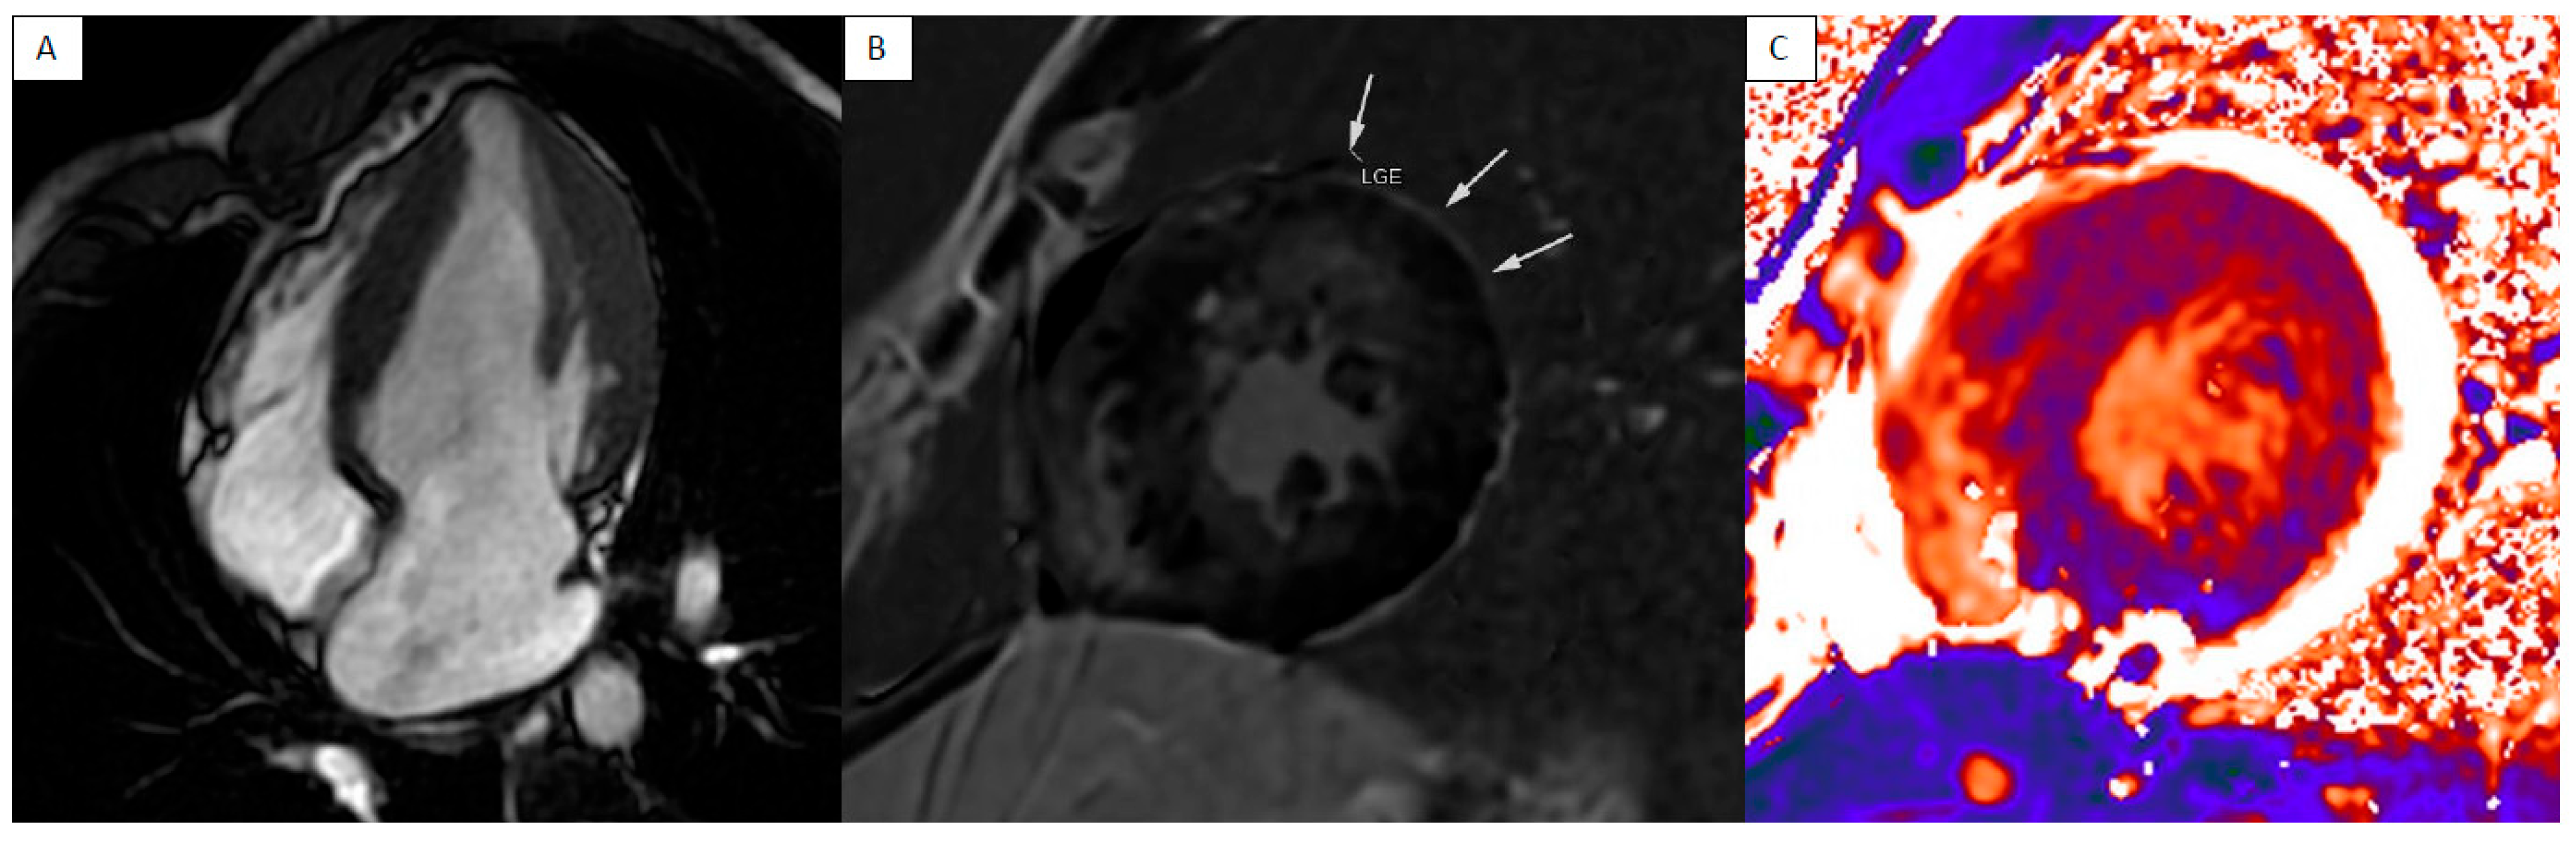

3. Cardiac Sarcoidosis